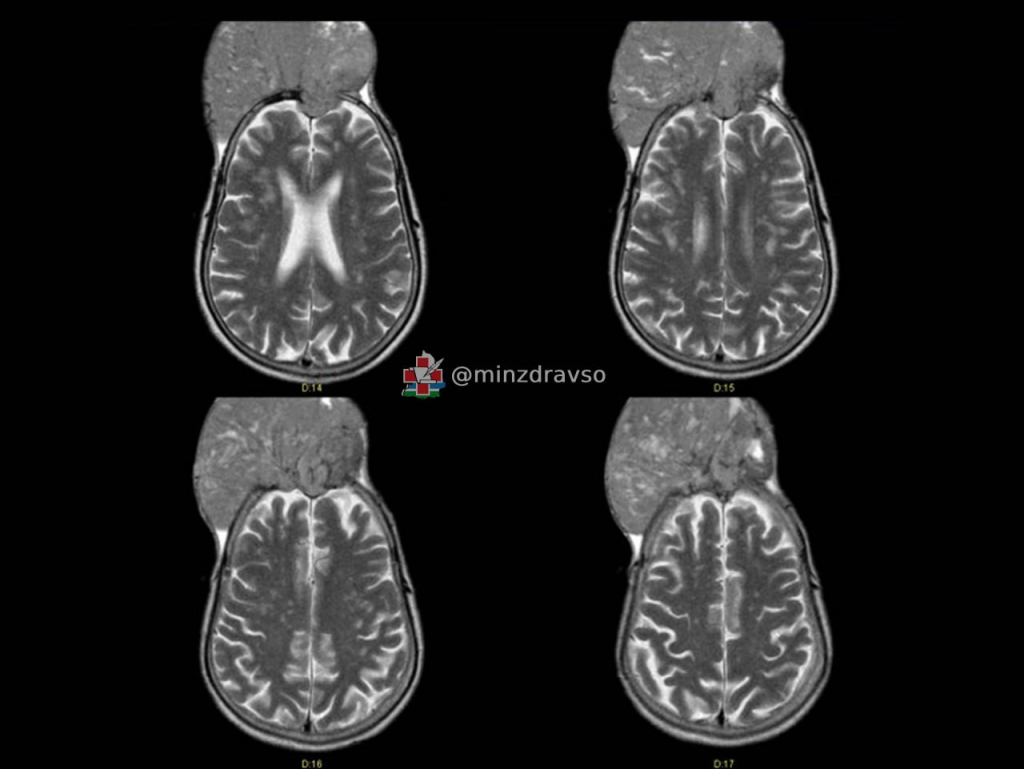

Так как такие опухоли питает обширная сосудистая сеть, хирурги сначала «закупорили» нужные сосуды, и лишь затем отделили менингиому от мозга. Позже пациенту сделали пластику оболочки и крупной вены, установили титановую сетку, протезирующую череп, выполнили пластику кожи и провели другие манипуляции для формирования анатомически правильной формы черепа. Операция длилась почти семь часов.

В свердловском Минздраве также отметили, что в приоритете нейрохирургов СООД не только сохранение здоровья, но и качества жизни пациентов, поэтому они стараются проводить операцию так, чтобы сохранять приятный визуальный вид.